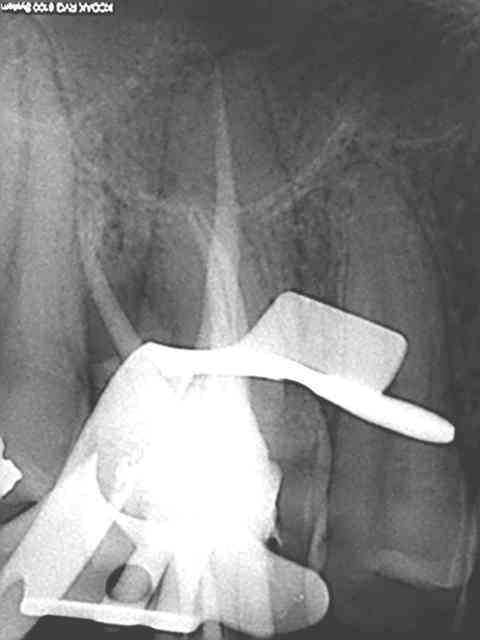

rte sur 16 au r25 un bonheur, le mv2 était imperméable au sx et s1 le r25 n'en a fait qu'une bouchée!

> rte sur 16 au r25 un bonheur, le mv2 était imperméable au sx et s1 le r25 n'en a

> fait qu'une bouchée!

C'est vrai, mais attention quand tu commences à faire des rte au reciproc tu te mets forcément à forcer un peu. La plupart du temps ça marche, et puis parfois ça fait de belles perfos !

Je ne l'utilise plus qu'au niveau apical sur les rte pour débloquer certaines situations.